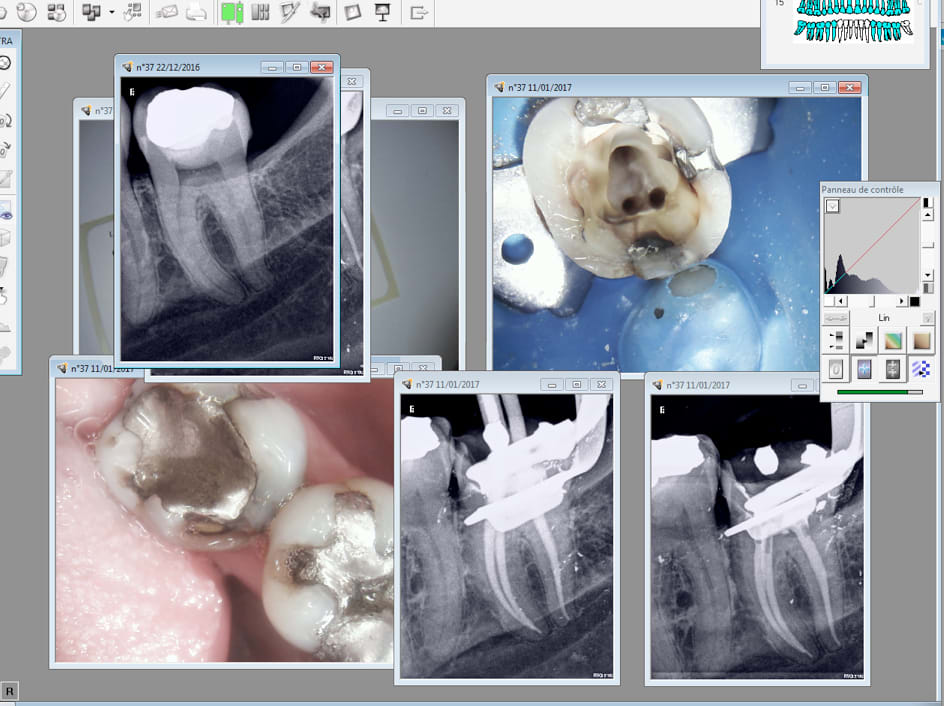

Mieux vaut ne pas laisser vivant une partie de la pulpe. -)

SX gold, S1 gold, réciproc blue.

J'ai mis une heure sur celle là. Because butées.

J'ai forcé comme un bourrin pour tester la résistance de ces instruments. Surprenant aucun n'a pété. -)

Capture d écran 2017 01 11 15.20 - Eugenol